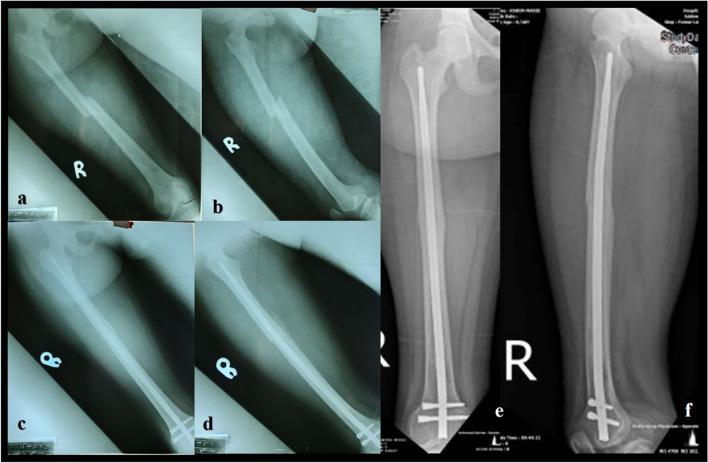

Femoral fractures are common in low and middle-income countries (LMIC), predominantly caused by high-energy trauma. The surgical implant generation network (SIGN®) program offers two different intramedullary nails in LMIC which are designed to be used without image intensifier free of charge for the patients: the SIGN standard nail (SSN®) and the SIGN Fin nail (SFN®). This study aimed to compare the results of the SSN® and the SFN® for the treatment of middle and distal shaft femoral fractures through a retrograde approach.

This was a retrospective, descriptive, and non-experimental study including all consecutive patients who underwent surgical management of middle or distal shaft femoral fracture between January 2017 and May 2022 in an NGO hospital located in Freetown, Sierra Leone. The duration of surgery, type of reduction, complications like screw loosening, implant migration, anterior knee pain and non-union rate at six months of follow up were evaluated.

A total of 122 patients were included in the study. Group A: 60 patients were managed with SSN® and Group B: 62 patients with SFN®. The mean operative time was 104 min with SSN® and 78 with SFN® (p < 0.001). Open reduction of the fracture was necessary in ten (16.7%) patients with SSN® and 12 (19.4%) patients treated with SFN® (p = 0.69). Non-union was observed in one (1.7%) patient with SSN® and two (3.2%) patients with SFN® (p = 0.57).

Both options seem equally effective in treating midshaft and distal femoral shaft fractures. The SFN® reduces the surgical time, due to this fact, in polytraumatized patients, patients with bilateral femur fracture or patients with ipsilateral tibia fracture, it can be considered as the best option to be used. There was no statistical difference in the complications presented by the two groups.